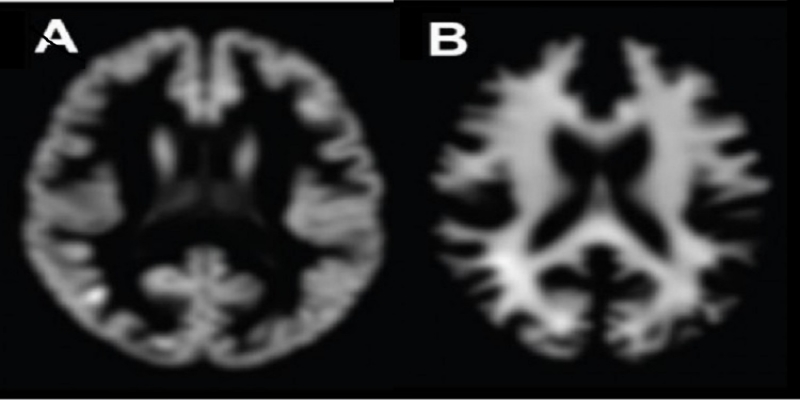

اما در این میان مشکلی وجود دارد؛ واقعیت این است که آنالیز سن مغز فرایند بسیار وقت‌گیری است، چون داده‌های به‌دست‌آمده از MRI باید مورد پردازش قرار گیرند تا در ادامه بتوانیم در مورد سن مغز اظهار نظر قابل اتکایی داشته باشیم. این پردازش شامل حذف بافت‌های غیرمغزی موجود در تصویر بالا است؛ بافت‌هایی مانند جمجمه؛ دسته‌بندی ماده‌ی سفید مغز؛ ماده‌ی خاکستری مغز. ضمن آنکه حذف ایرادات خود عکس نیز از طریق تکنیک‌های حذف نویز و هموارسازی داده‌ها انجام می‌شود.

یادگیری عمیق یا یادگیری سلسله‌مراتبی، زیرشاخه‌ای از یادگیری ماشینی و بر مبنای مجموعه‌ای از الگوریتم‌ها است؛ این روش یک تکنیک استاندارد برای یادگیری عمیق است. مونتانا به همراه همکارانش از ۲۰۰۰ شخص سالم ۱۸ تا ۹۰ ساله MRI مغزی گرفتند. این اشخاص هیچ‌گونه مشکل مغزی نداشتند، بنابراین سن مغزی و سن تقویمی آن‌ها با هم منطبق بود. این اسکن‌ها از نوع استاندارد T1-wieghted MRI بودند که توسط مدرن‌ترین دستگاه‌های MRI انجام شدند. نتیجه‌ی هر اسکن حاوی برچسبی بود که سن تقویمی شخص روی آن نوشته شده بود.

هم‌زمان، تیم تحقیقاتی تصمیم گرفت روش یادگیری عمیق را با روش‌های مرسوم تعیین سن مغز مقایسه کند. برای این کار به پردازش گسترده‌ی اطلاعات برای شناسایی ماده‌ی سفید مغز و ماده‌ی خاکستری مغز نیاز بود. همچنین در ادامه باید از یک روش تحلیل آماری به نام رگرسیون فرآیند گاوسی (GPRR) استفاده می‌شد.